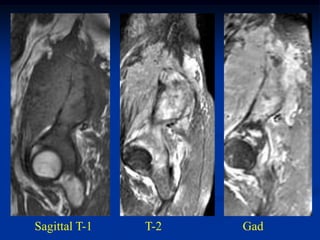

Case #888.1         Ewing’s Fibula

15 yr male with pain and swelling of leg for 3 months

Cor T-1   T-2   Gad

Axial T-1   T-2

Gad